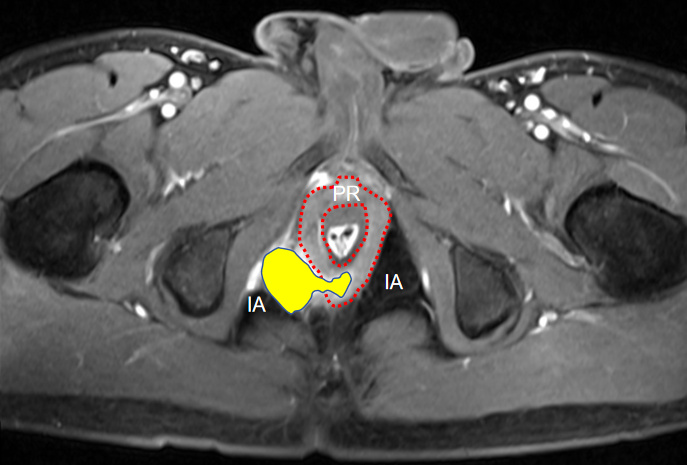

他们先给王先生做了详细的专科检查——王先生的肛周外观看着完全正常,可肛门指检时,能摸到右侧粘膜饱满、压痛,6 时位的肛窦还能触及硬结、压痛。肛周 MRI 更是清晰显示,瘘管主支像 「隧道」一样穿过肛管直肠环,突破肛提肌,并合脓肿形成。最终明确诊断为「高位复杂性肛瘘」。

结合王先生的症状、体征及影像结果,李裕波手术团队进行深入的术前讨论:肛门括约肌就像控制排便的「闸门」,高位肛瘘的瘘管刚好绕在「闸门」周围,此时治疗需要权衡治愈率和肛门功能保护,既要把瘘管和脓包清干净,又不能在过程中碰伤括约肌,否则会导致大便失禁,终身遗憾。

TROPIS(经肛括约肌间切开术)作为目前一种新兴的肛瘘保留肛门括约肌手术,其核心原理是:①经肛门切开肛门内括约肌,开放内外括约肌间隙,清除感染源。②保留外括约肌,减少对肛门控便的影响。③引流脓腔或瘘管,达到二期愈合。